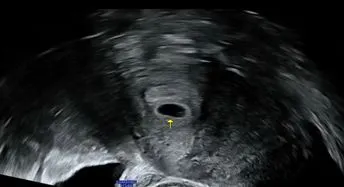

드디어 초음파 보는날.

[여기 아기집이 보이네요~ 난황도 있구요.

좋은 위치에 착상 되었고 자궁 내막도 이정도면 안정적이에요.

축하드려요~ 임신 입니다!]

정말이지 너무나도 신기한 경험이었다.

내 뱃속에 생명이 자란다니.

5주 5일 정도라고 하셨고

손에 들린 초음파 사진을 한참을 들여다 봤다.